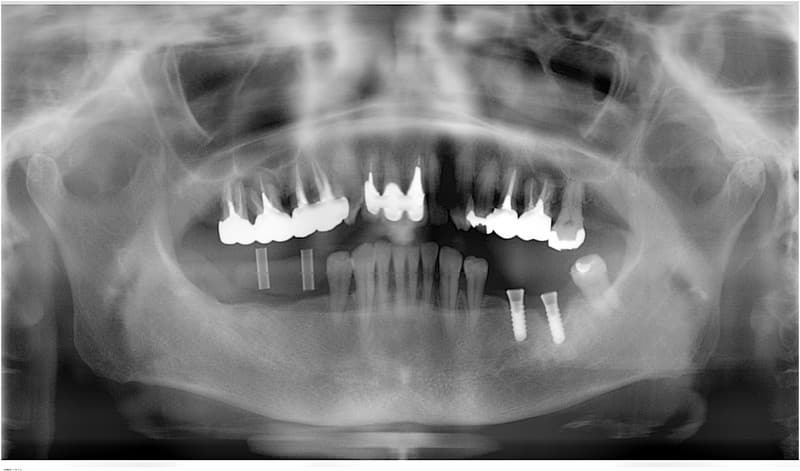

- 外科処置によって顎の骨にインプラントを埋め込みます。

- 3~6ヶ月後にインプラントに人工の歯を連結するためのパーツを取り付けます。

(小外科処置を伴います。)

技工士さんがあなただけの人工の歯をカスタムメイドで製作します。

人工の歯をインプラントに連結して完成となります。